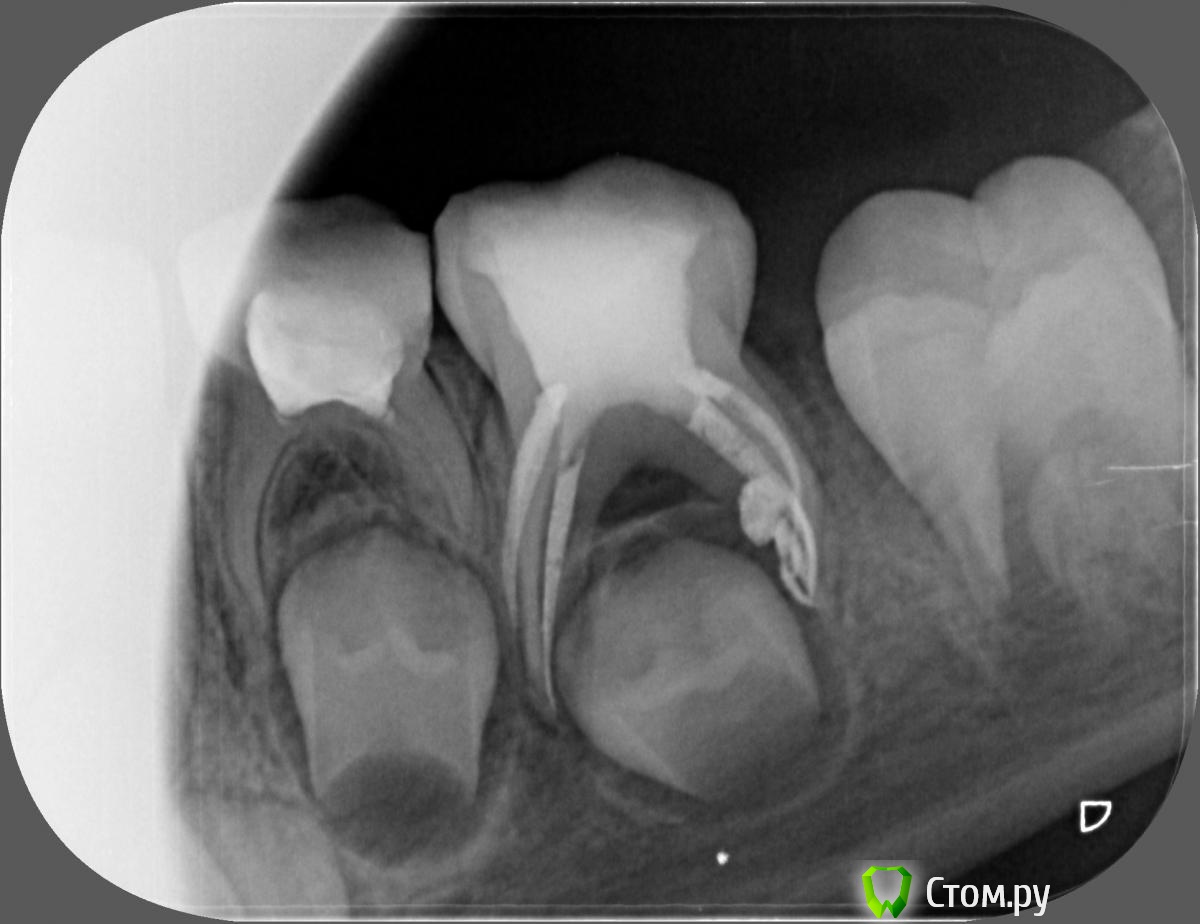

Джима Опубликовано 9 ноября, 2013 Поделиться Опубликовано 9 ноября, 2013 (изменено) нормально завернули в устьях гейтсами, потом ручными файлами чуток доработать и всё. в любой книжке по детству : В МОЛОЧКАХ НЕ РАБОТАЮТ ЭНДОМОТОРАМИ. на удалённых молочных попробуйте - перфо по малой кривизне увидите.да и зачем? там того канала-то... вся рабочая длина 10-12мм я Н-файлы применяю. а почему не применяют? Изменено 9 ноября, 2013 пользователем Джима 2 Ссылка на комментарий

Джима Опубликовано 12 ноября, 2013 Поделиться Опубликовано 12 ноября, 2013 чёт верится с трудом. Вы тут наколочку дали на свежий учебник 2013г по детству, с Даггалом, я заказала, должны привезти послезавтра. Вот там и посмотрим Честно, не представляю, зачем это в молочках... Там гейтсом устье продавил на 2-3мм, плюс высота коронки 4-6мм, остаётся дочистить максимум ещё 5мм, и канал там обычно достаточно широкий. Даггал рекомендует Н-файлы не больше 30 номера, я скребусь 20-25 или сразу 25, моем и пломбируем. А если эндомотором, то чем? и зачем? имхо, ими больше в стенки затрёшь и в канальцы по малой кривизне, чем выскребешь. не, я пока при своём, может, что-то и изменится. 4 Ссылка на комментарий

kalitka Sergei Опубликовано 19 ноября, 2013 Поделиться Опубликовано 19 ноября, 2013 сколько времени к вас уходит на обработку каналов?По-разному, зависит от того как сидит ребенок, на сколько хорошо открывает рот. Этапы: снимок, анестезия, коффердам, доступ к к.к., обработка каналов (механическая + ирригация), заполнение метапексом, контрольный снимок занимают около 40 минут, в среднем. 2 Ссылка на комментарий